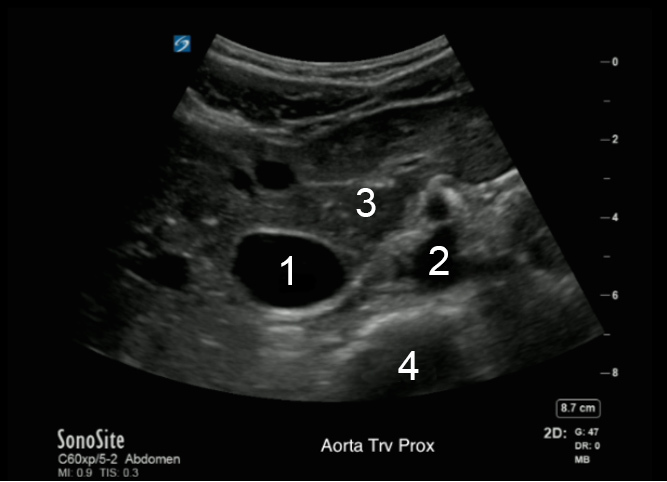

Aorta Proximal Transverse Image

Inferior Vena Cava (IVC)

Aorta

Liver

Spine